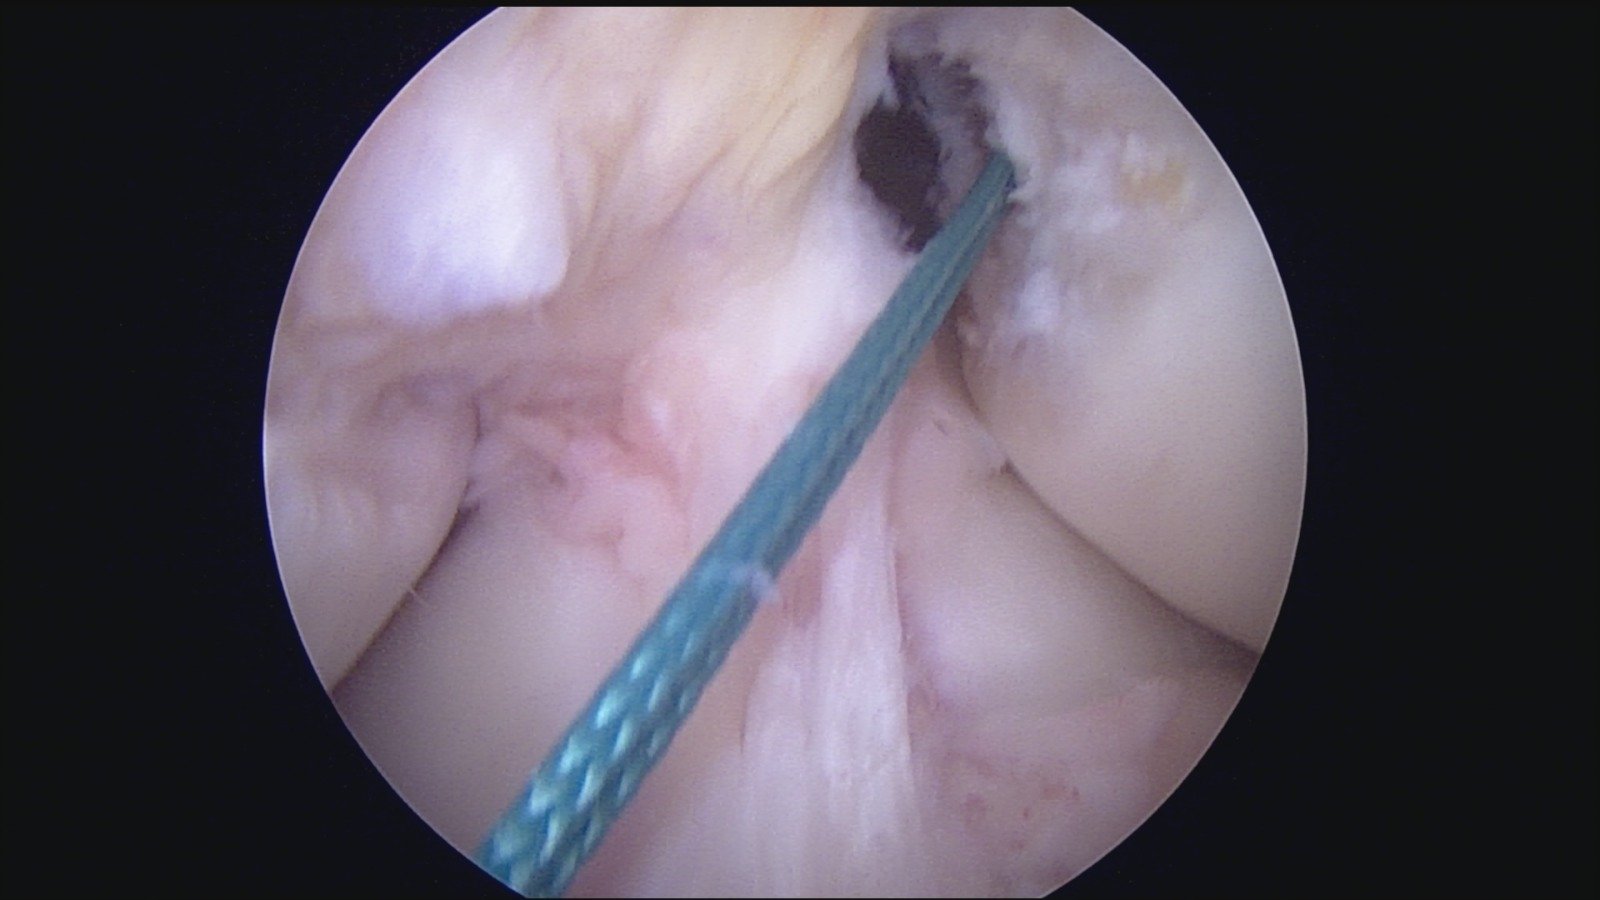

GalleryShoulder rotator cuff repair Meniscus root repair Meniscus repair Bankart repair for recurrent shoulder dislocation ACL reconstruction Machines Instruments